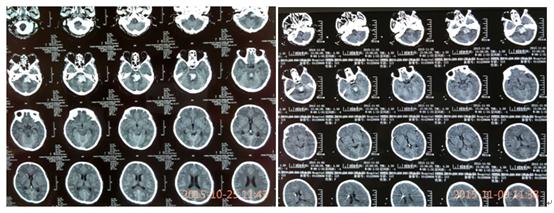

治疗前后,患者脑部影像图像对比

入住重症监护病房后,创伤脑血管神经外科主任金永健博士高度重视,迅速组织脑血管病医疗团队为患者进行了留置口咽通气道改善通气,降压、止血、健脑等治疗,并请麻醉科紧急会诊行气管插管、呼吸机辅助呼吸,经上述急救,患者病情略稳定。但2天后,患者意识障碍加重呈深昏迷态势,频繁恶心、呕吐,双侧瞳孔中央位、散大固定,复查头颅CT提示:脑干出血进一步增多、量约14ml,全脑干出血破坏脑干上行激活系统,并破入四脑室,梗阻性脑积水!患者病情再次告病危!金主任立即决定在床旁局麻下行“双侧脑室外引流术+换能器植入术”,缓解颅内高压并持续监测患者颅内压力变化。术后,患者意识障碍无明显缓解,舌后坠明显、呼吸困难伴痰液增多,中枢性高热40℃以上伴应激性溃疡;针对颅内高压,主管医生立即予以尿激酶溶通四脑室积血,恢复脑脊液循环;床旁行“气管切开术”管理呼吸道,予以冰毯机物理降温,亚低温治疗减轻脑水肿和降低脑耗氧量及颅内压,冰盐水及止血药物3小时一次胃管注入控制胃肠道出血;期间患者循环系统紊乱,心率较快、达130-170次/分,科室遂请心内科会诊协助控制心率;患者血管挛缩、输液困难,在B超导引下留置PICC成功,保证临床救治工作的有序进行。后科室再请呼吸内科会诊,协助控制肺部感染。在全科医护人员及多学科通力协作下,患者的病情终于得到了控制,成功度过了脑干出血最危险的第4天、第5天、第6天、第7天!

患者病情稳定一周后,复查头颅CT提示:脑积水明显缓解,但仍有交通性脑积水,难以耐受夹闭脑室引流管24小时,所以不能拔除引流管,否则仍会出现急性脑积水导致生命危险。而长期留置引流管又会加重患者脑室感染的风险,针对患者本人来说也是雪上加霜、难以承受的风险,可能会葬送之前的所有努力!阴云再次笼罩在医护人员及患者家属的心里,患者家属因难以支撑这种病情的反复变化及现实的压力,多次要求自动出院听天由命,但关键时刻的放弃或者是犹豫,结局就是死亡!救治团队重头审视病情,思索解决的方案,决心间断夹管并辅助腰椎穿刺的传统做法,终于,在2周的时限内成功拔管,患者的颅内压监测始终在10mmHg正常范围内,并且在2天的时间内成功复温,从亚低温恢复正常体温,没有高热、惊厥、休克及心率紊乱等复温过程中常见的合并症;再视察了3天,患者生命体征均较平稳,并且存在情感反应,在住院17天后顺利出院,回家继续康复(高压氧)治疗。